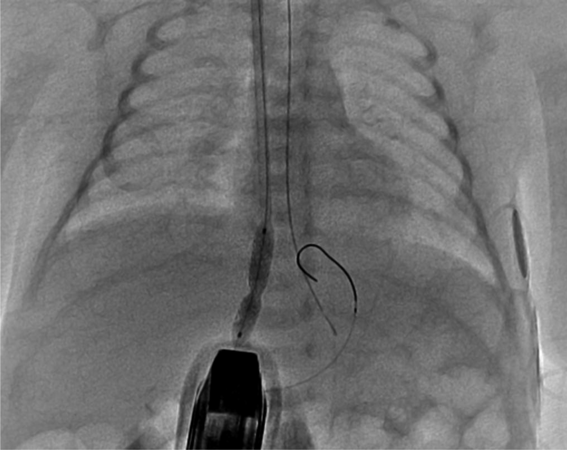

総肺静脈還流異常症(下心臓)に対する静脈管ステント留置後の新たな再狭窄評価法Novel Method to Evaluate Restenosis after Ductus Venosus Stenting for Infracardiac Type Total Anomalous Pulmonary Venous Return